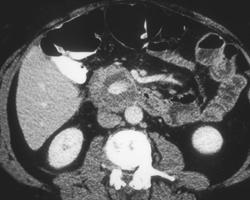

Cancer of the Body of the Pancreas